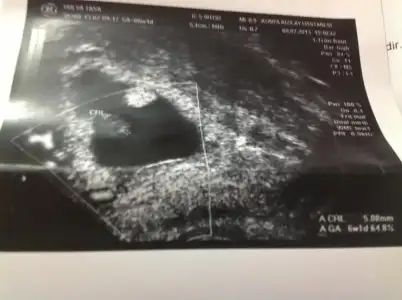

geldim doktordan ve Rabbime binlerce şükürler olsun herşey yolunda. veeee pıt pıtlarımızı da duyduk. sabah deli gibi su içtim rahatca görebilelim diye. çok işe yaradı maşallah... ben bu kalp atışlarından sonra hamilelik sevincini yaşamaya başladım, eşim de aynı şekilde:) bugün akşama kadar ağzım kulaklarımda dolaşacam sanırım:))) ultrasonda pıt pıt diye sesleri duyunca bi ara gözlerimi kapattım ve o sesin tadını çıkardım... eşimi görmeliydiniz, gözleri cam gibi parlıyodu ekrana bakarken.. ohh dedik bi rahatladık çok şükür. ya kızlar, çok farklı bi duygu içimde atan bi kalp taşıyorum mucize bu işte:) Çok samimi yazıyorum, Allah bütün hamişlerimize önce keseleri, sonra pıt pıtları, sonra güüzel test sonuçlarını, sonra kolay doğumları nasip etsinnn... Amin...